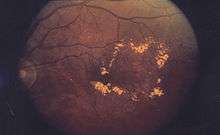

| A 61-year-old man with medical history of type 2 diabetes that presents a macular edema, evidenced by an OCT (the edema marked with arrows). The central image is a 3D reconstruction of the retinal thickness (the edema is coloured in red). | |

Macular edema occurs when fluid and protein deposits collect on or under the macula of the eye (a yellow central area of the retina) and causes it to thicken and swell (edema). The swelling may distort a person's central vision, because the macula holds tightly packed cones that provide sharp, clear, central vision to enable a person to see detail, form, and color that is directly in the centre of the field of view.